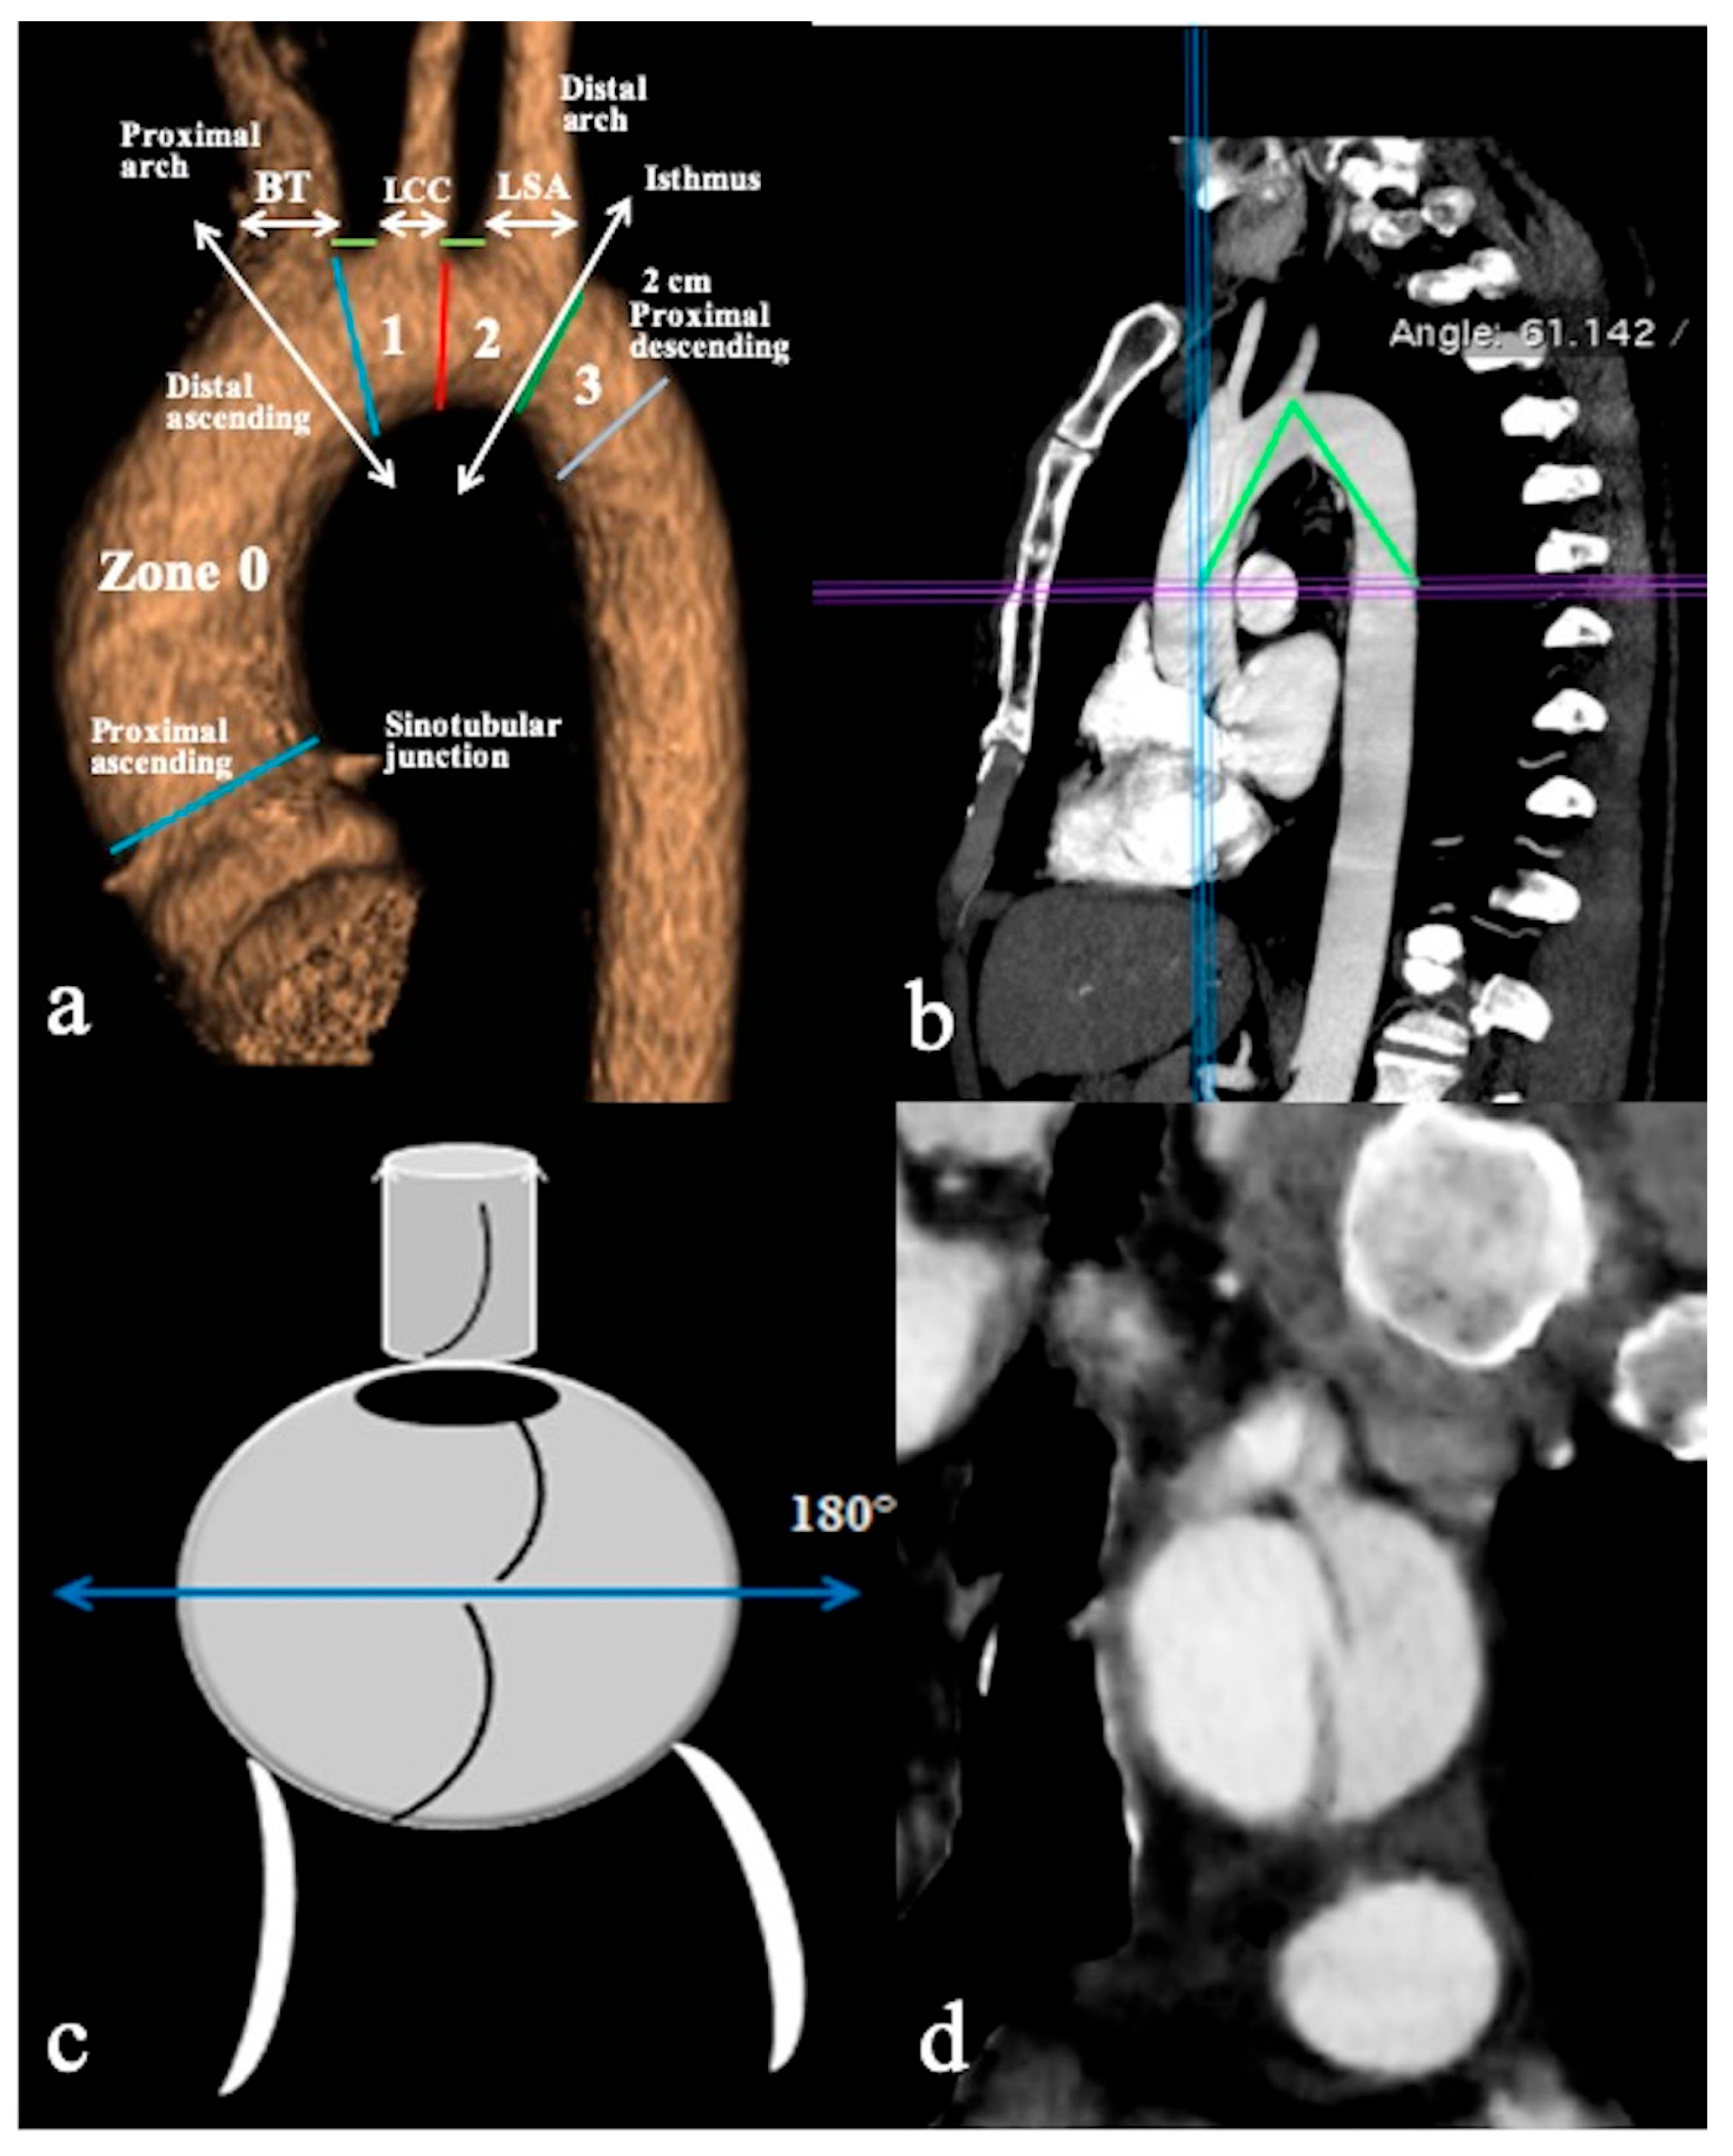

- In Configuration 3 (Arch entry), the primary ET is situated within the aortic arch, and the flap extends into the DTA without affecting the ascending aorta [38]. This Configuration 3 occurred in 7 (19%) patients (Figure 5a,b). This AD configuration was already described as proximal type B dissection according to 2010 AHA guidelines [7] and recently reported as arch B group AD from IRAD [38] and as non-A non-B acute AD with entry tear in the aortic arch [39,40]. In this configuration, the ET was often located in the greater curvature of the arch (4/6), while in one case (1/7) its location was not clearly identified. In total, 4/7 of these patients underwent hybrid and 2/7 surgical therapy.